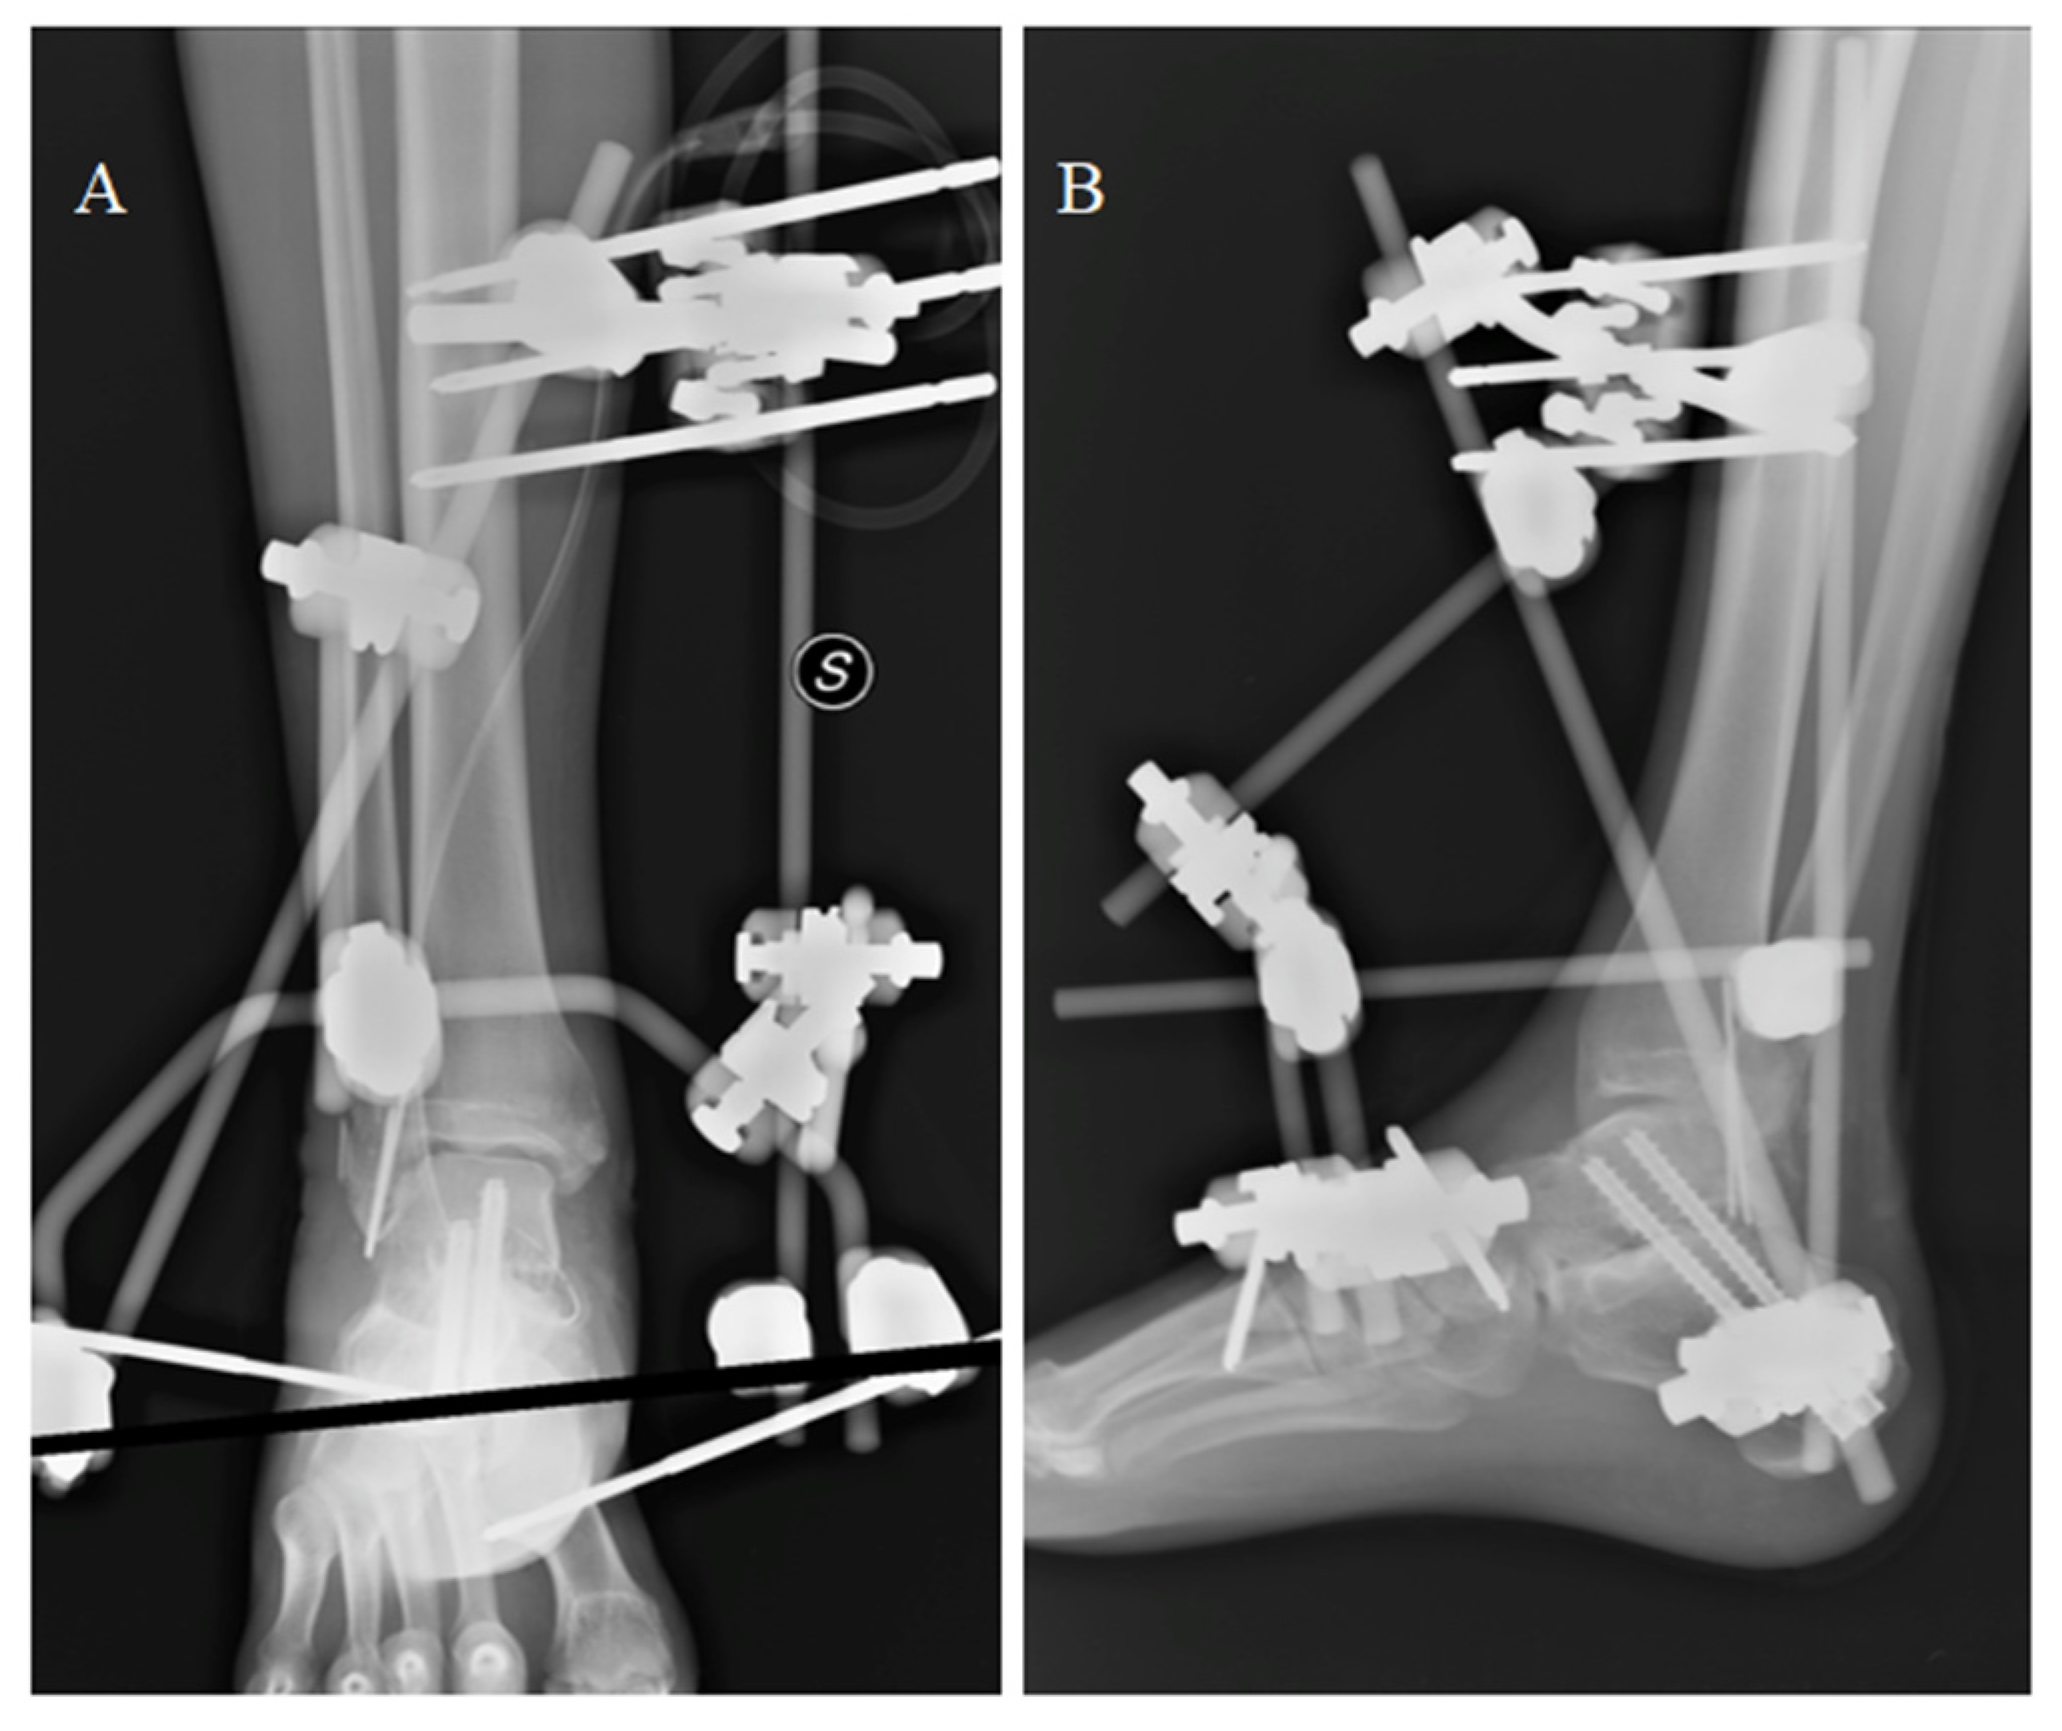

During the second year of follow-up, the patient experienced a worsening, up to the impossibility of walking without pain. He soon started complaining of painful plantar flexion and morning stiffness. A ROM limitation (ROM = 20°) was observed at the control visit. Two years after surgery, antero-posterior and latero-lateral ankle radiographs suggested a secondary osteoarthritis with articular space narrowing, implying the indication for a prosthesis revision (Figure 9). Either arthrodesis or tibial resurfacing were proposed as management options. In this case, the patient expressed the desire to maintain ankle function: A conversion to total ankle arthroplasty with TTR was performed. The tibial prosthesis consisted of a tibial trabecular titanium (Ti6Al4V) component and 6 mm-thick, high-density polyethylene (Figure 9). The lengthening of the Achilles tendon was performed using a percutaneous technique.

Figure 9.

Two-year post-surgery X-ray of the implant from antero-posterior (A) and latero-lateral (B) projections. Articular space narrowing and osteophyte formation (compared with Figure 7) can be observed (A,B). The total talar replacement after revision surgery from antero-posterior (C) and latero-lateral (D) projections. Image courtesy of Dr. Paola Verde Aerospace Medicine Department, Aerospace Test Division, Pratica di Mare, Rome, Italy.

After surgery, the patient was enrolled in a rehabilitation program based on continuous passive movement; progressively, partial weight bearing was allowed. Total weight bearing was conceded after 3 months.

Conversion to total ankle arthroplasty achieved a positive outcome: After every 1-year follow-up (up to 5 years), the patient complained of little to no pain and reached 35–40° of total sagittal ROM. After one year, the patient was judged fit to fly, and after two years, he resumed flying on high-performance jets. The outcomes were stationary at the last follow-up, 5 years after surgery. The aforementioned revision surgery and the implications and observations concerning specifically Aerospace and Aviation Medicine have been presented and discussed in detail in the Journal of Aerospace Medicine and Human Performance by Verde and colleagues [].